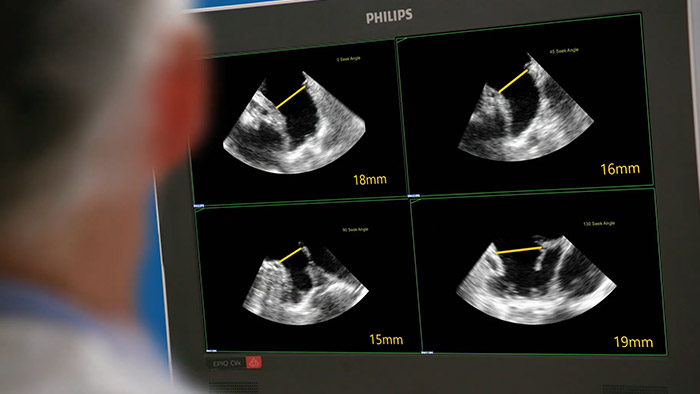

左心耳を迅速かつ簡単に、直観的に評価。

EchoNavigatorでは、超音波とX線の情報が1つの画面に表示(Augmented visualization)され、ガイダンスおよびデバイスと組織の関係評価に使用できます。 LAA閉鎖術において、EchoNavigatorでは、次のことを実行して手技効率を向上させることができます。